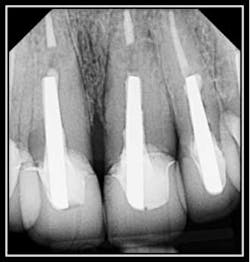

By Dr. John Y. Kwan Vertical root fractures typically extend through the long axis of the root toward the apex and commonly occur in endodontically treated teeth. Depending upon the severity of the fracture, an interdisciplinary and/or multidisciplinary approach may be required for functional and esthetic rehabilitation of the tooth. Intraosseous fractures typically create deep, narrow, sharply defined isolated periodontal pockets and radiographic examination may reveal unilateral thickening of PDL along the fracture side of the root. If the fracture is not apparent radiographically, diagnostic tests may be considered using a bite-test, transillumination test, or confirmation of the VRF via surgical exploration. Confirmation of root fractures with Perioscopy provides the most minimally invasive, non-surgical method available. The below photo and corresponding video clearly show a vertical root fracture.